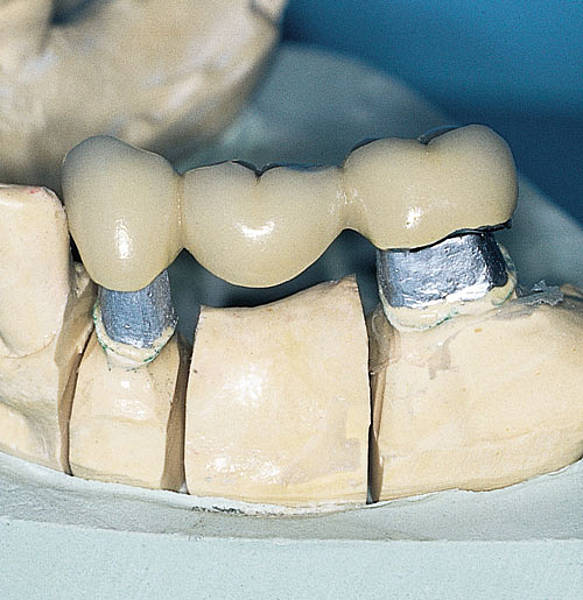

Стоматология: коронки и мостовидные протезы

Раздел: Кадры-советчики